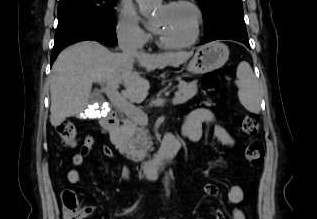

腹部

尿管結石

胆石